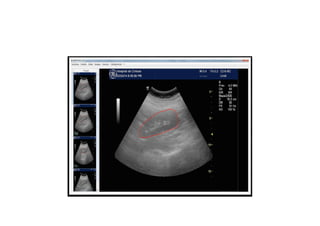

Ultra Sound Imaging Used routinely by nephrologists Non ionizing Repeatable Affordable

• 5.

But US imagingis Usually only qualitative User dependant Volume estimated by formula 2D image only for DICOM Poor documentation for ECR